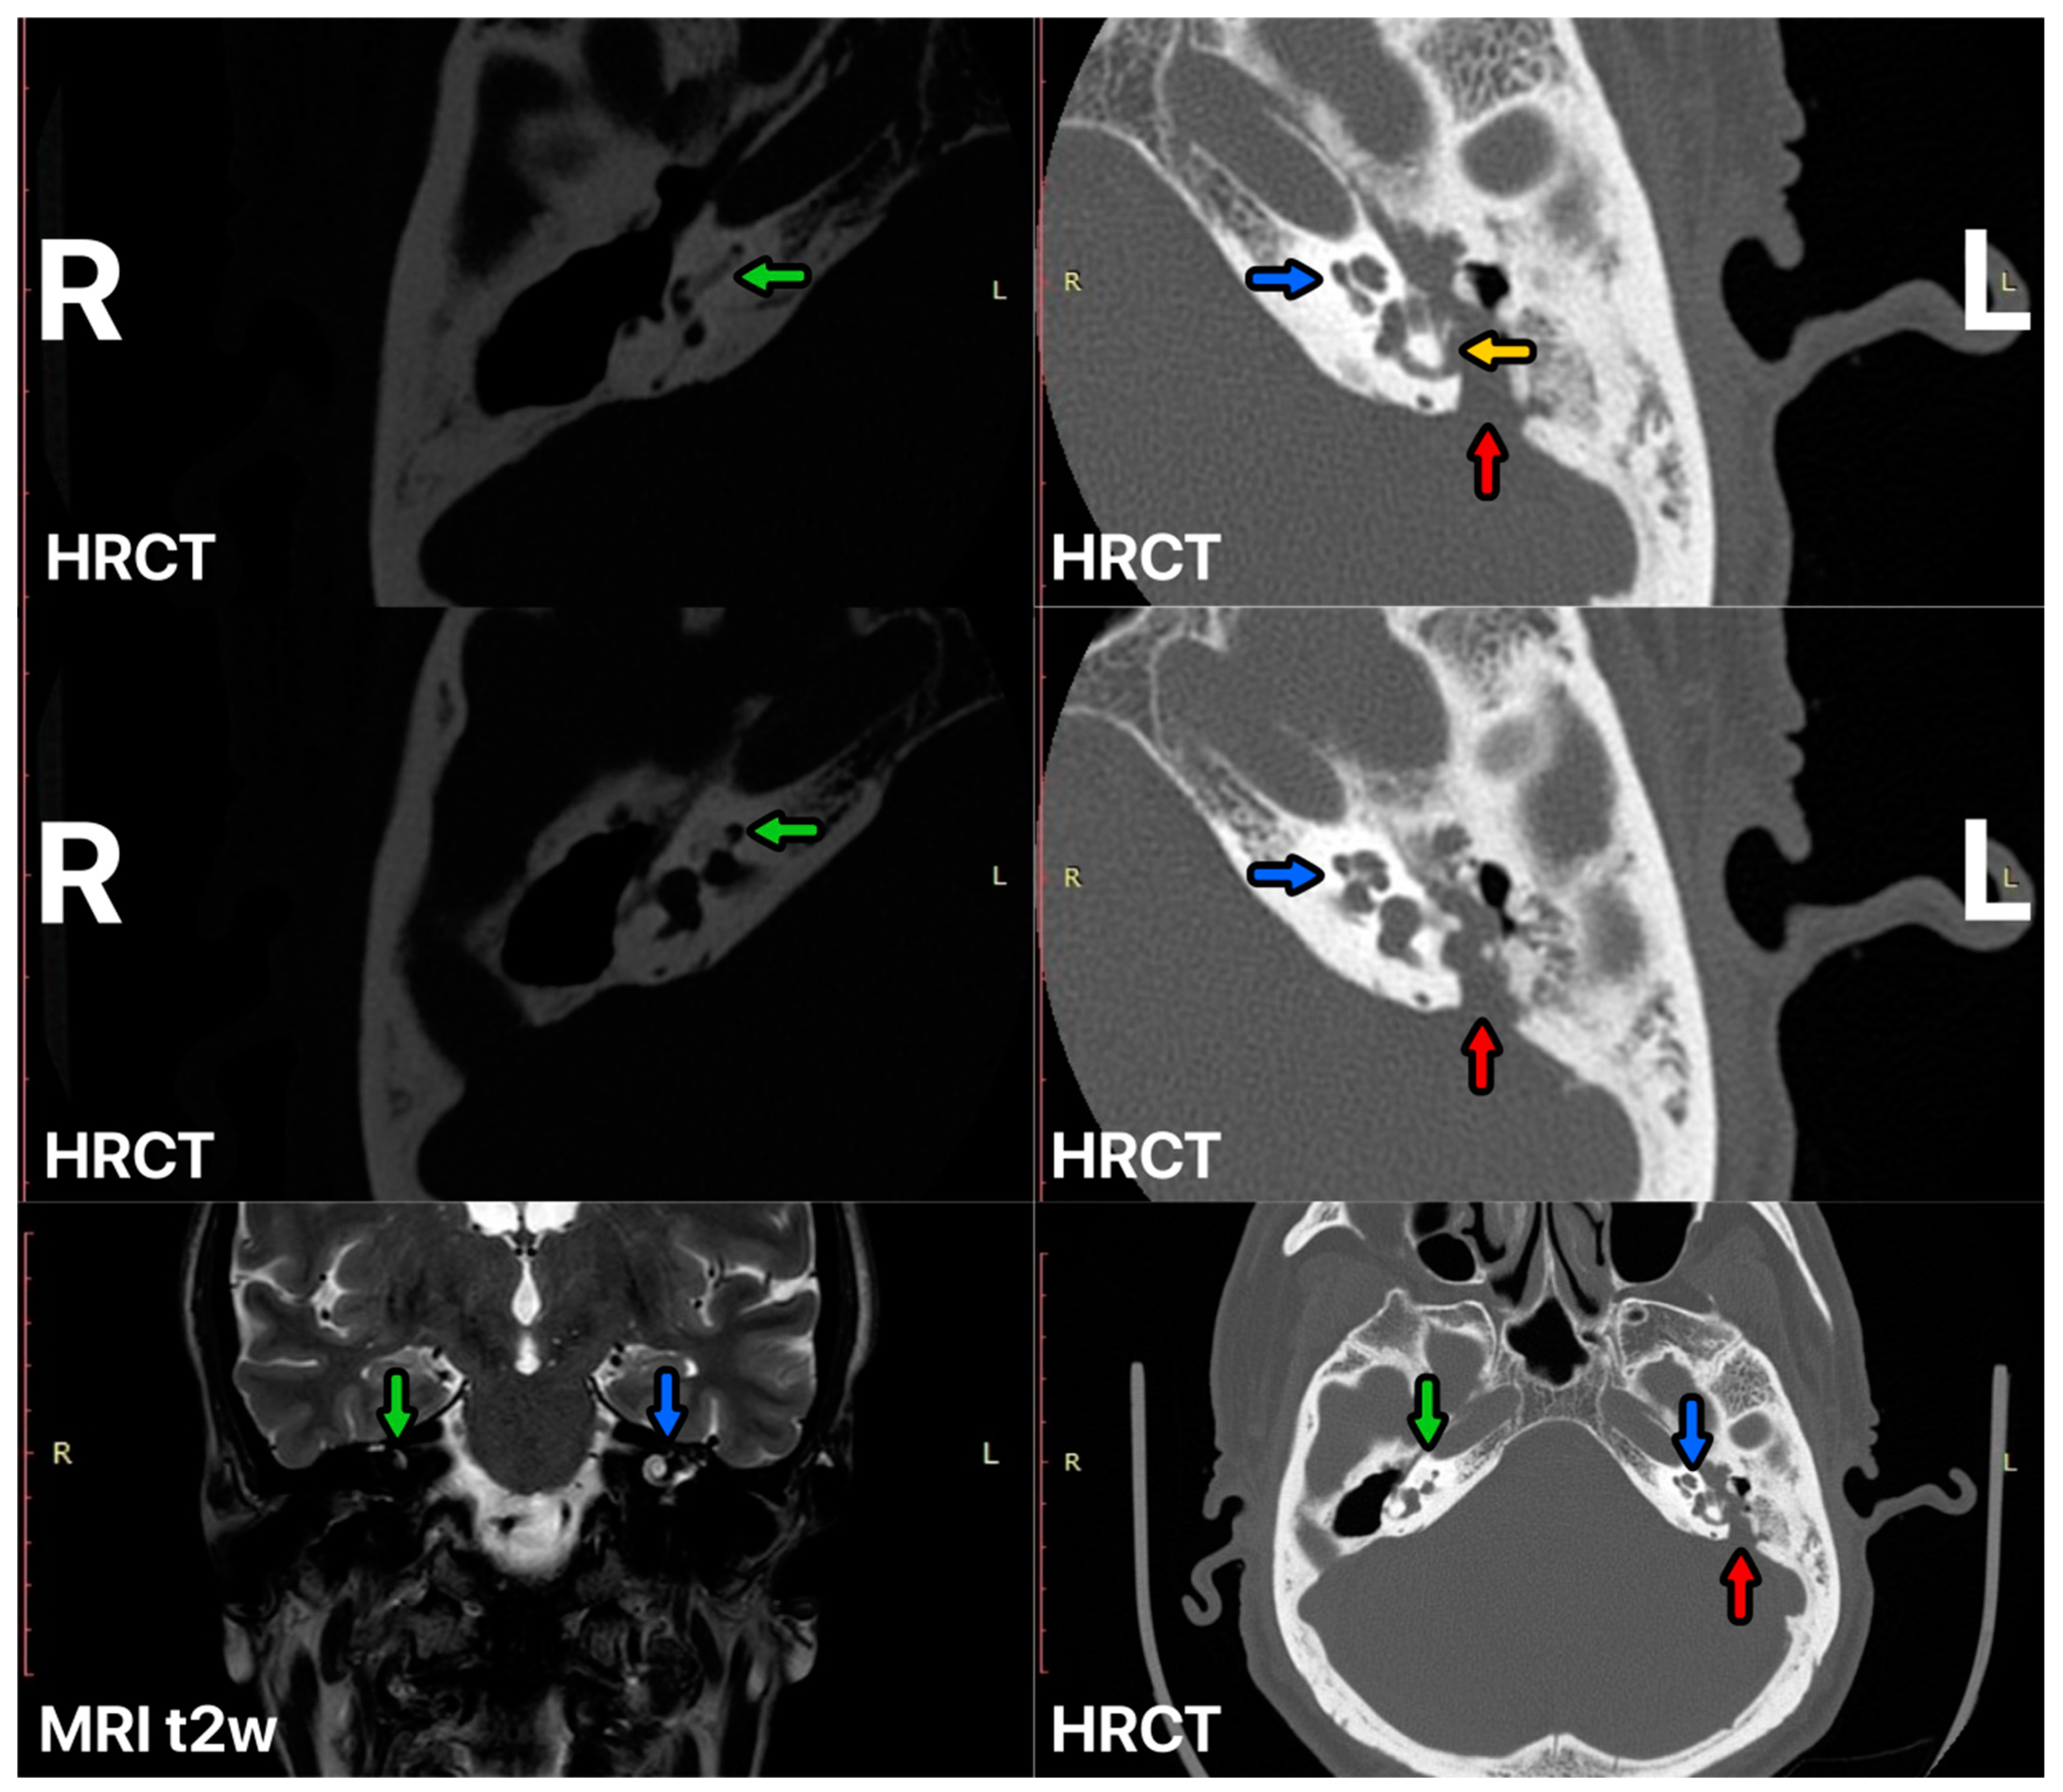

3.1. Case 1